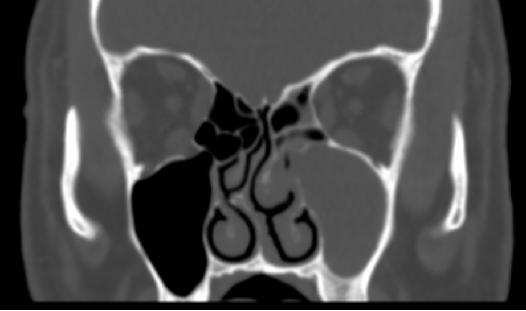

B:影像特点1:双肺多发结节,2部分结节周围可见晕征,3可见空洞,内壁很光整,4未见胸腔积液和淋巴结肿大。空洞的话,中性粒细胞和白细胞不是很高,不考虑金葡菌那种空洞。空洞内壁光整,其余结节周围有晕征,不考虑肺癌并多发转移。结核的话壁薄,卫星灶啊,好发位置啊,病程相对较长,也不考虑。其实隐球菌是不除外的,当然了,一查血管炎自然肯定考虑韦格纳肉芽肿了。这个人做了鼻窦。

②:临床综合性表现:常见就是鼻窦,鼻塞或者出血之类的,伴有肾炎,中耳炎、皮下结节等;